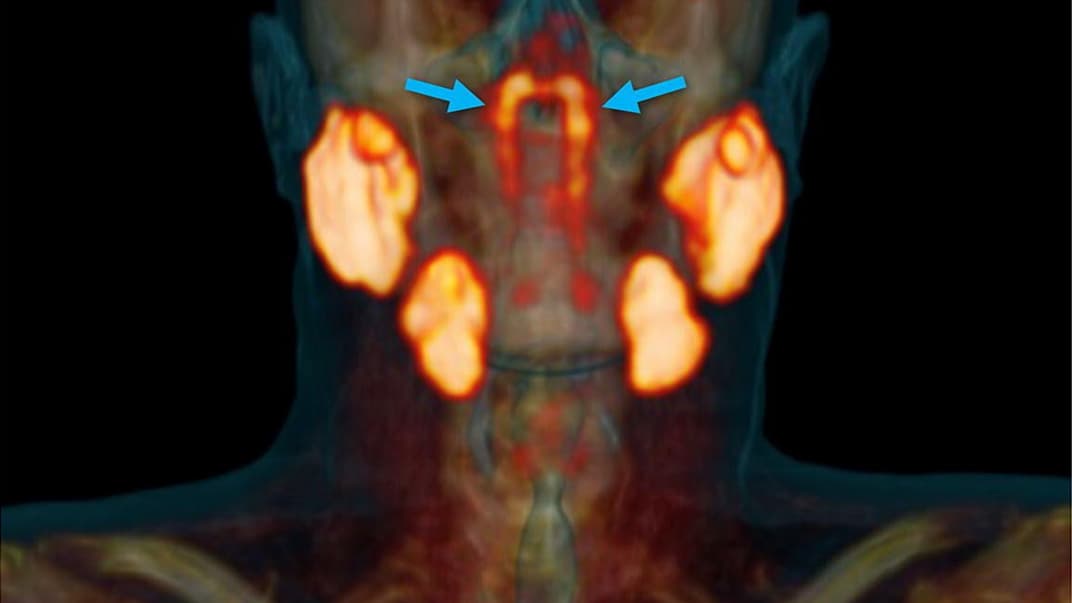

Новую, четвертую группу слюнных желез исследователи из Института рака в Нидерландах обнаружили случайно при поиске клеток рака простаты с помощью сочетания компьютерной томографии и позитрон-эмиссионной томографии — PSMA PET-CT.

Во время сканирования методом PSMA PET-CT врачи вводят в организм пациента радиоактивный «детектор»: он обнаруживает белок глутаматкарбоксипептидазу II, или PSMA. Этот белок присутствует в клетках рака простаты и, по совпадению, в ткани слюнных желез.

И во время одного из таких сканирований исследователи во главе с онкологом Воутером Фогелем обнаружили новую пару слюнных желез длиной около 4 сантиметров в месте, где носовая полость сообщается с глоткой. Это примерно посередине нашей головы.

Чтобы убедиться, что это не совпадение, ученые проверили результаты PSMA PET-CT еще для 100 пациентов — и обнаружили у них ту же пару слюнных желез. Их же нашли и физически — при вскрытии тел двух человек.

Новый орган исследователи предлагают назвать трубноваликовыми слюнными железами, потому что он расположен над трубным валиком — возвышением в носовой части глотки, где расположен хрящ слуховой трубы.